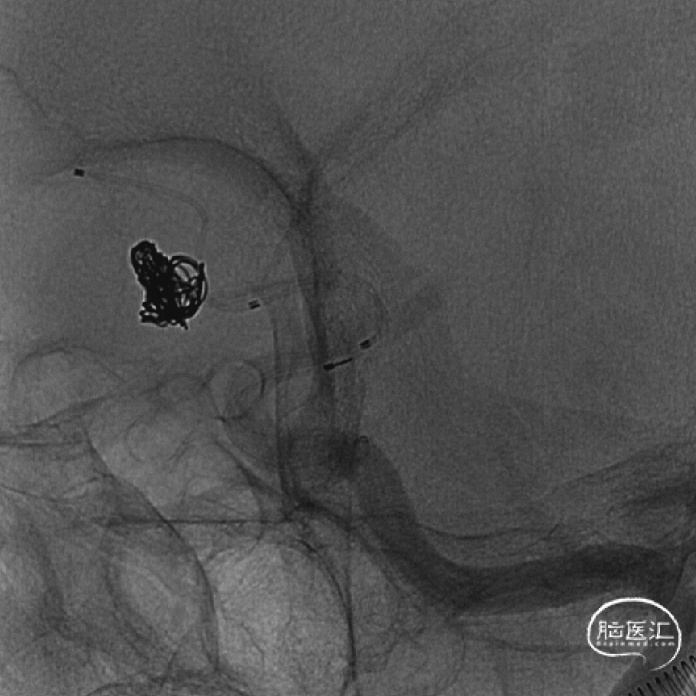

术前影像

术前DSA影像

术后影像

释放支架后继续填塞至动脉瘤不显影。双侧A1-A2显影良好。患者术后神经体检正常。